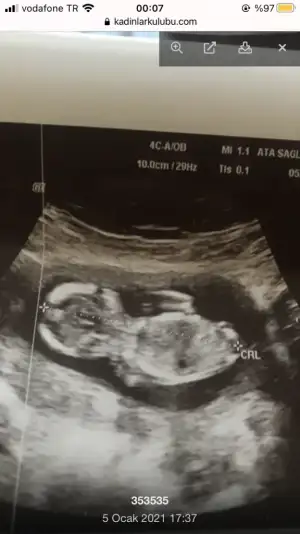

Eki Görüntüle 2764653 doktor da Kıza benzetti. Çizebilir misiniz rica etsem. Teşekkürler.